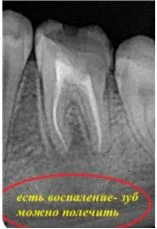

- осложнения, вызванные проведением лечения внутри канала;

Давайте сравним снимки зубов, сделанные при помощи визиографа (слева), и при помощи компьютерной томографии (справа).

Как говорится, ощутите разницу. КТ - гораздо более точная и своевременная диагностика.

Воссоздавая орган (зуб) или даже совокупность органов, необходимо предельно точно знать исходную ситуацию. Корни зубов, каналы зубов, крупные сосудисто-нервные пучки, идущие внутри костной ткани, верхнечелюстная пазуха во всех подробностях и т.д. - в неискаженном виде все это можно увидеть только на компьютерной томограмме. Стоит ли говорить, что все эти структуры важны для имплантации, так как могут быть легко поврежденфы в ходе операции.